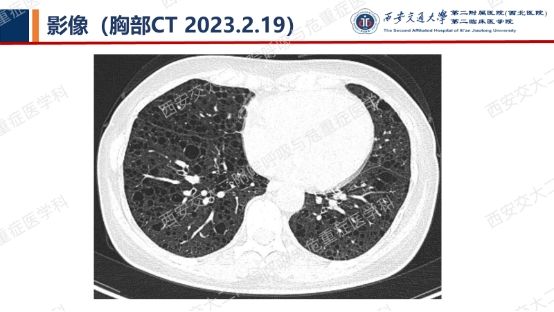

阅影探案,析病寻踪 // 第一期(上)

结合以上患者病史及胸部CT,第一诊断分别考虑???欲知答案,且看后期!!!